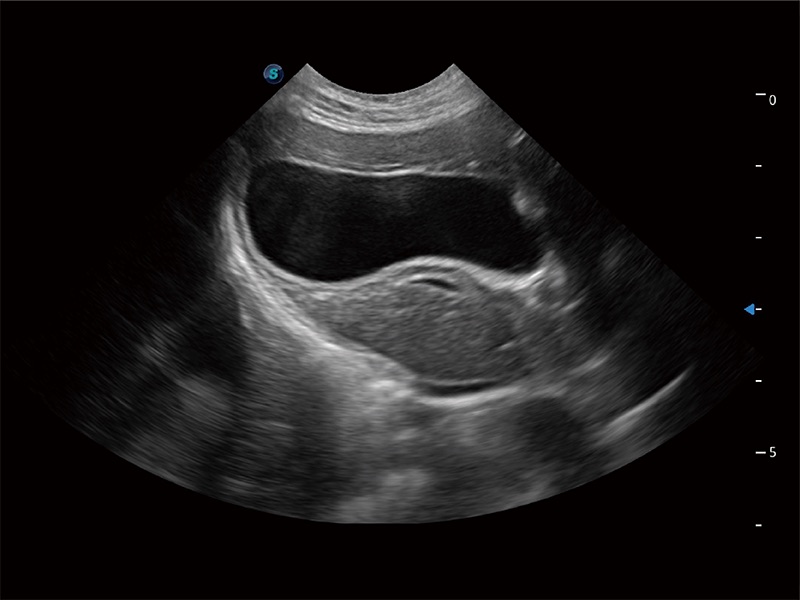

动物是人类最亲密的朋友和最值得信赖的伙伴。美狮贵宾会官网也一直致力于探索动物专用的超声影像解决方案。全新推出的ProPet系列,是美狮贵宾会官网在动物超声影像智能化、专业化、精准化的一次跨越式革新。动物不能用言语来表述自己的不适,通过超声影像,ProPet系列搭建了动物医生与不同物种沟通的“桥梁”,为动物医生注入了“治愈之力”。 ProPet 80 是美狮贵宾会官网匠心打造的一款高端动物专用彩超,采用性能卓越的全新硬件架构,极大提升超声系统的运行效率和数据处理能力,帮助动物医生从容应对日益增多的挑战性病例和日益多样化的临床需求。

高性能和先进的临床应用工具可以为动物医生提供临床信心。ProPet 80 搭载了先进的腹部和浅表应用工具,帮助医生在日常临床实践中发挥前所未有的作用。

ProPet 80 专为动物医生设计,对不同的动物体型和生理结构作出了针对性的优化。通过动物影像专用软件,可满足个性化的应用需求,帮助动物医生获得更精确的诊断数据。

ProPet 80 全新的动物超声智能软件和丰富的探头群,为动物医生提供了高清晰度和精细分辨率的图像,无论在宠物、马科、畜牧还是实验室动物等应用中都可以轻松应对,为您的日常工作带来满意的体验。